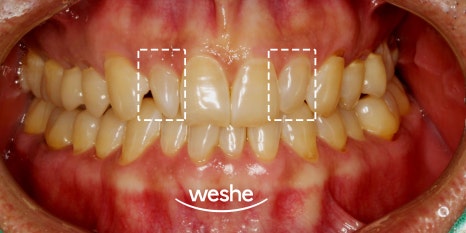

1.왜소치(peg lateralis)란?

정상치아 보다 작고 뾰족한 모양으로

'peg lateralis'라고도 부르는데요.

주로 위턱 측절치,

위턱의 앞니 중 두번째에 위치한 부위에

흔하게 나타나며

12, 22번 부위의 peg lateralis 상황에서

이것을 적용하는 경우가 있는데요.

마곡역 치과 에서는

앞니 왜소치는 단순히 크기만 작은 것이 아니라

형태적인 문제도 같이 동반하는 경우가 많다

판단하고 있습니다.